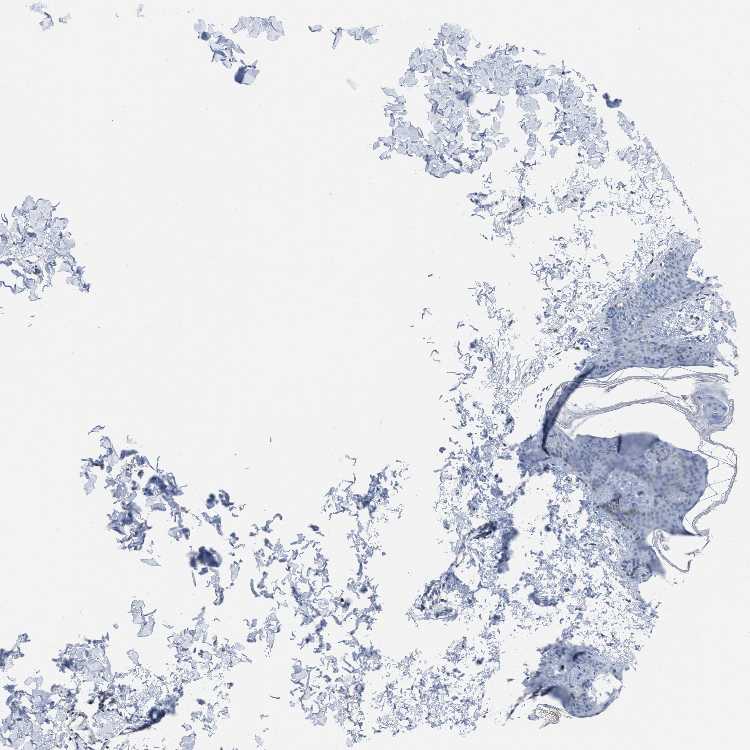

SKIN 1 - Antibody stainingi

Antibody staining in the annotated cell types in the current human tissue is reported as not detected, low, medium, or high, based on conventional immunohistochemistry profiling in selected tissues. This score is based on the combination of the staining intensity and fraction of stained cells.

Each image is clickable and will lead to virtual microscopy that enables deeper exploration of all samples and also displays staining intensity scores, fraction scores and subcellular localization as well as patient and tissue information for each sample.

Antibody HPA018976Antibody HPA029591

Langerhans Not detectedNot detected

Fibroblasts Not detectedNot detected

Keratinocytes Not detectedLow

Melanocytes Not detectedLow

SKIN 2 - Antibody stainingi

Antibody HPA029591

Epidermal cells Medium